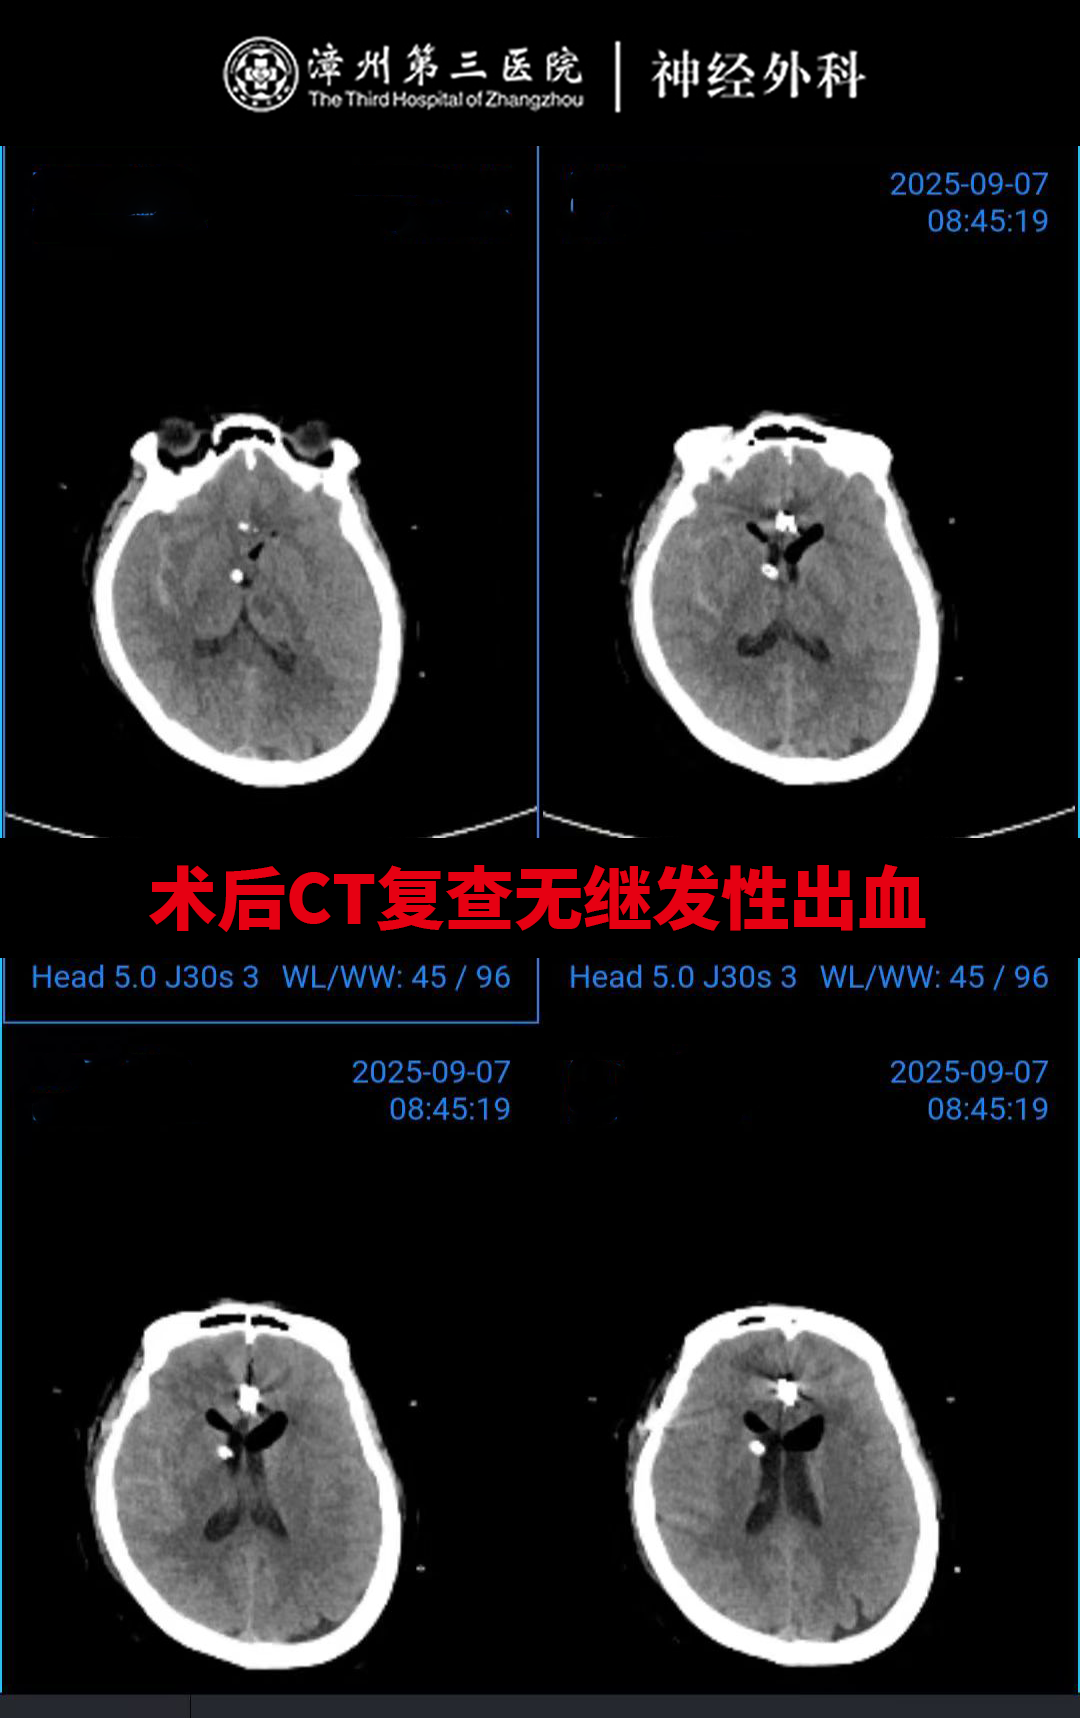

神经外科团队第一时间紧急会诊,深知这颗“复杂炸弹”的凶险:位置深、形态不规则,宽颈分叶的结构,且与周围的血管关系密切,让手术夹闭难度陡增,加上深夜突发,必须与时间赛跑,神经外科团队经过详细的术前讨论,迅速敲定“纵裂入路分区并列组合夹闭动脉瘤”。主刀医生神经外科卢炜鹏主任凭借多年深耕脑血管病领域的经验,在显微镜下精准操作,逐一分开动脉瘤周围复杂结构,将分叶的瘤体分区夹闭,同步引流颅内积血、置入颅内压监测装置。整个手术紧张有序,最终成功“拆弹”,未伤及周围正常组织。

术后,医护团队紧盯颅内压变化,细致做好呼吸道护理与生命体征监护,用专业干预严防再出血、助力积血排出。如今的黄姨恢复很好,意识清楚,行走自如,无任何并发症,已恢复正常生活。